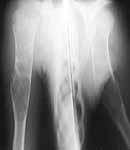

This 12 yr old boy was treated by me in May 2002 for pathological fracture right humerus conservatively. Curettage and bone grafting was suggested but parents were not willing. Xrays taken on 6th July 2002 shows the fracture united. He was protected by an Alkathin Brace for the Right Arm.

6-7-02